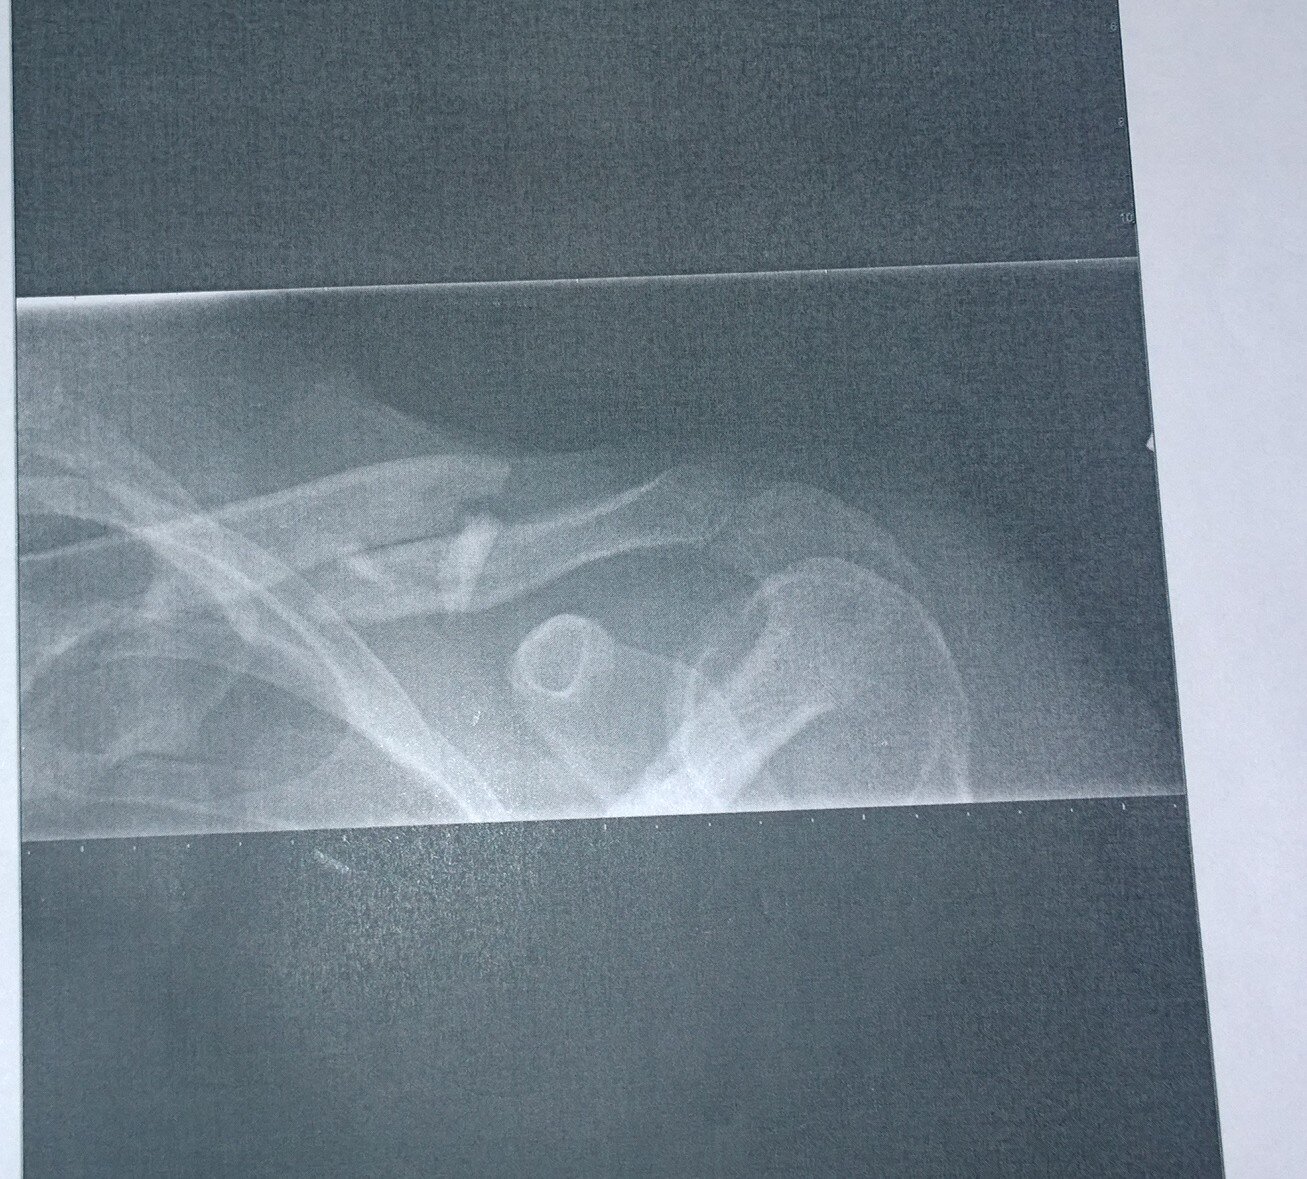

tPq9yYlUyXGyWM3WcvY8MdpsKyGiDRoY7Ace84Je4ZWelcome_to_a_comet2234dma-66dma-226WP_20141114_001WP_20141114_002WP_20141114_003WP_20141114_004WP_20141114_005OUCH!! It's Broken

2014-11-14 11/14-15/14